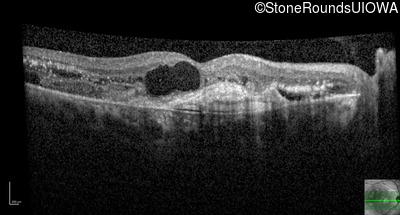

Age at visit: 59 years (Visit 3)